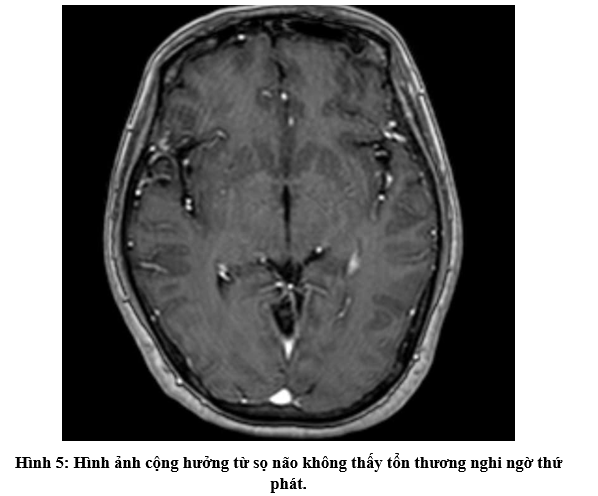

- Chụp cắt lớp vi tính ổ bụng: Không phát hiện tổn thương bất thường.